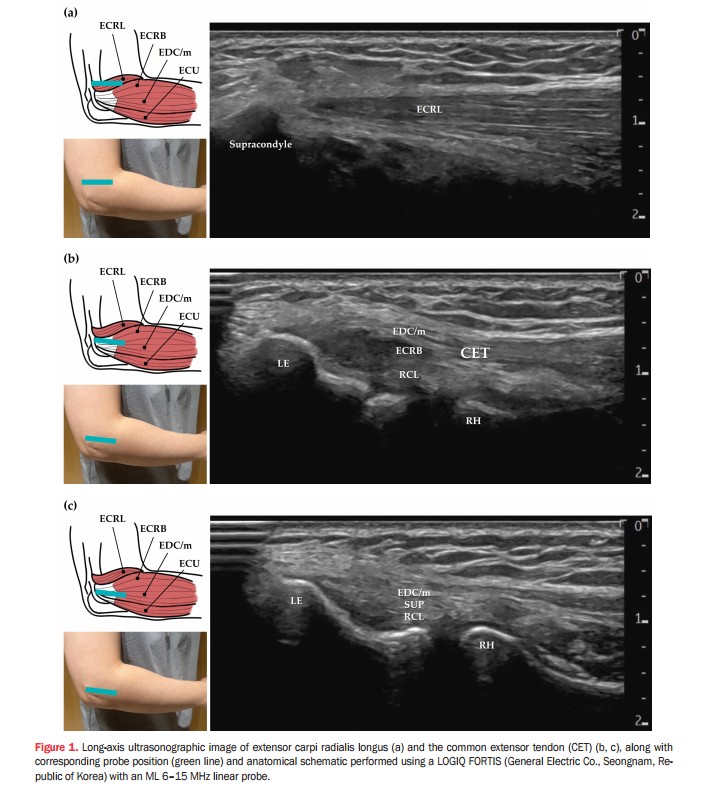

이를 해결하기 위해 주료(LI12) 혈자리의 ‘상완골 상과’를 해부학적 랜드마크로 삼아 상완골 외상과에 부착하는 공통신전근 힘줄 전체를 체계적으로 평가하는 표준화된 경혈 초음파 프로토콜을 제시했다.